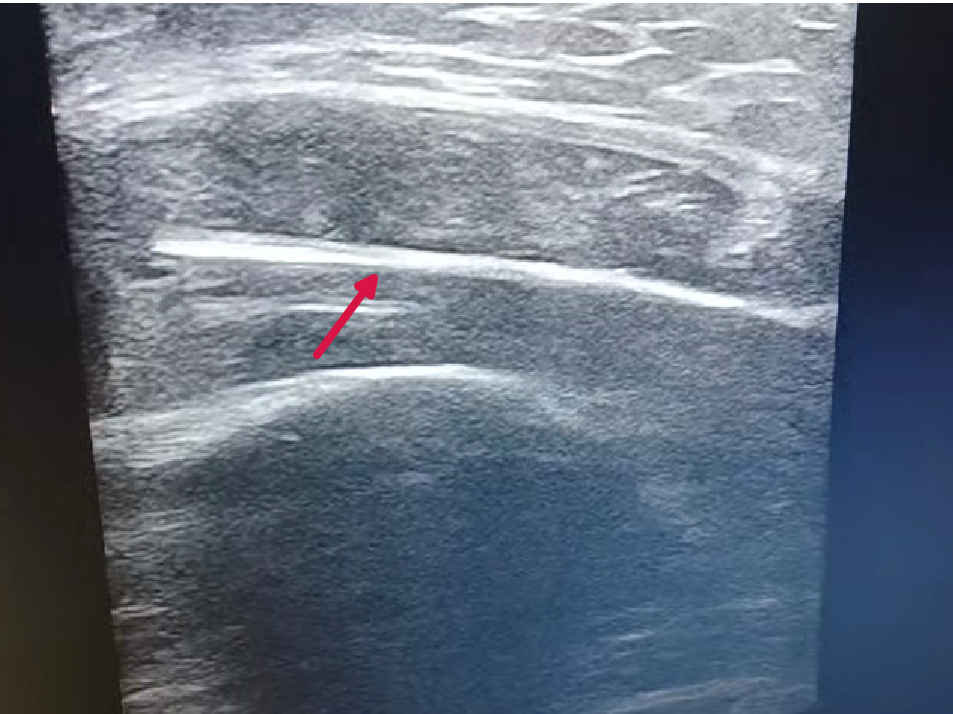

超声下的异物影像

为实现“精准微创”治疗目标,骨科团队邀请超声中心主任李红平会诊,李主任接诊后,手持探头在患者手臂伤口周围细致探查,同时引导患者活动肢体,屏幕上清晰显示异物如何随肌肉牵拉发生细微移位,其与邻近小血管的安全距离也一目了然。在随后的手术中,超声中心医师全程手持探头跟踪异物位置,骨科医师则在实时影像引导下,精准避开血管和神经,最终将数块碎片完整取出。术后邱女士刺痛感即刻消失,坦言“原本担心要挨一大刀,没想到医生用‘探头’引导就解决了问题,恢复又快又省心。”